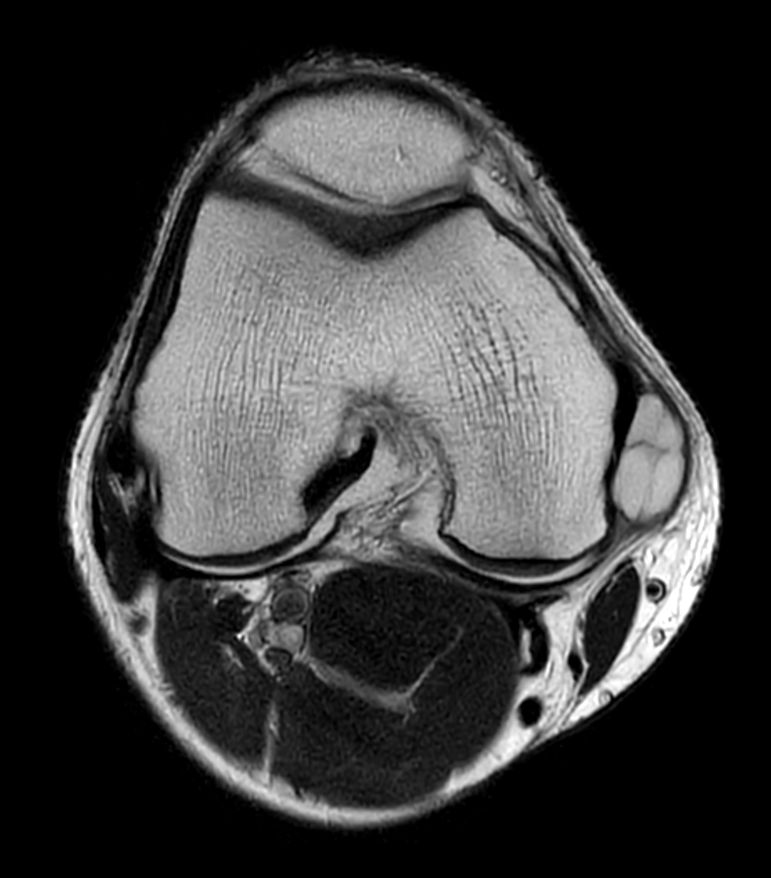

Knee with lesion

Patient with a Knee lesion. Compressed SENSE is used to shorten the total exam time.

T2w TSE - Compressed SENSE